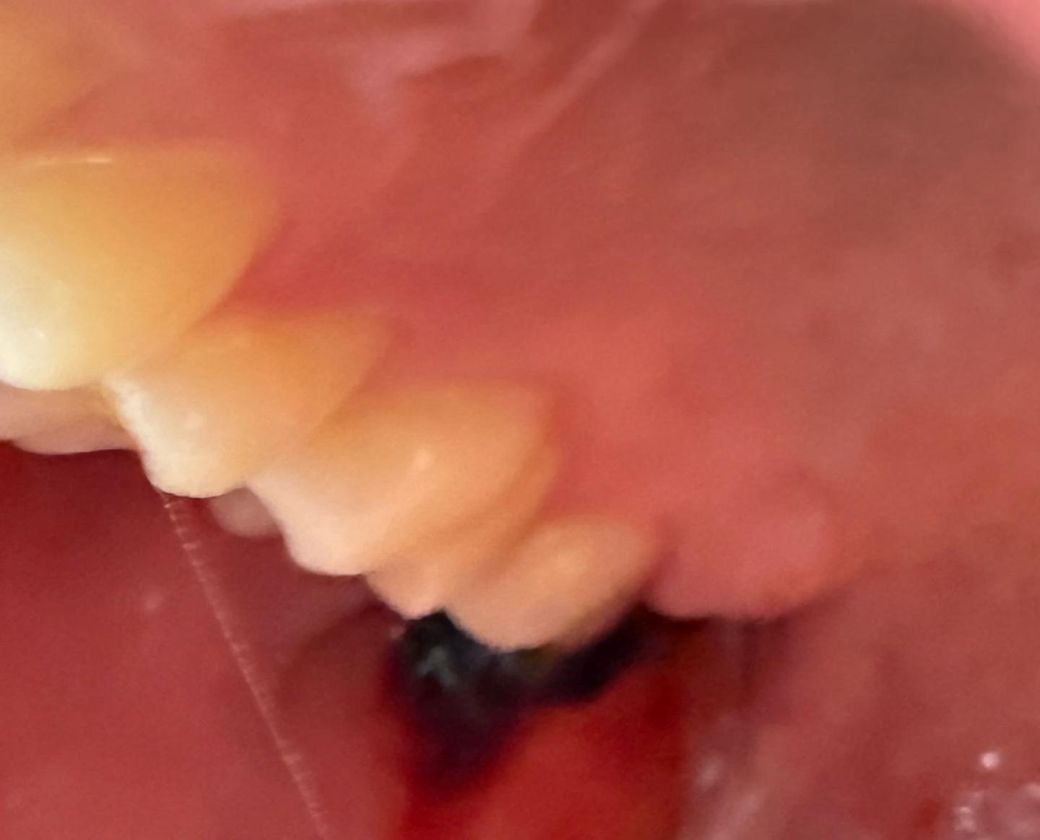

거즈를 빼고 조금 지나서 보니까 피떡이 조금 밖으로 빠져나온듯 한 느낌이 드는데 괜찮을까요?

피떡이 아예 빠진 느낌은 아니고 살짝 걸려있는 듯한? 매달려 있는 듯한? 느낌이 듭니다. (이를 물면 어금이에 피떡이 씹히는 느낌이 듭니다.)

• 1번 째 사진

이미 빠져나온 혈병은 치유에 의미없으니 가볍게 끊어서 빼내셔도 됩니다